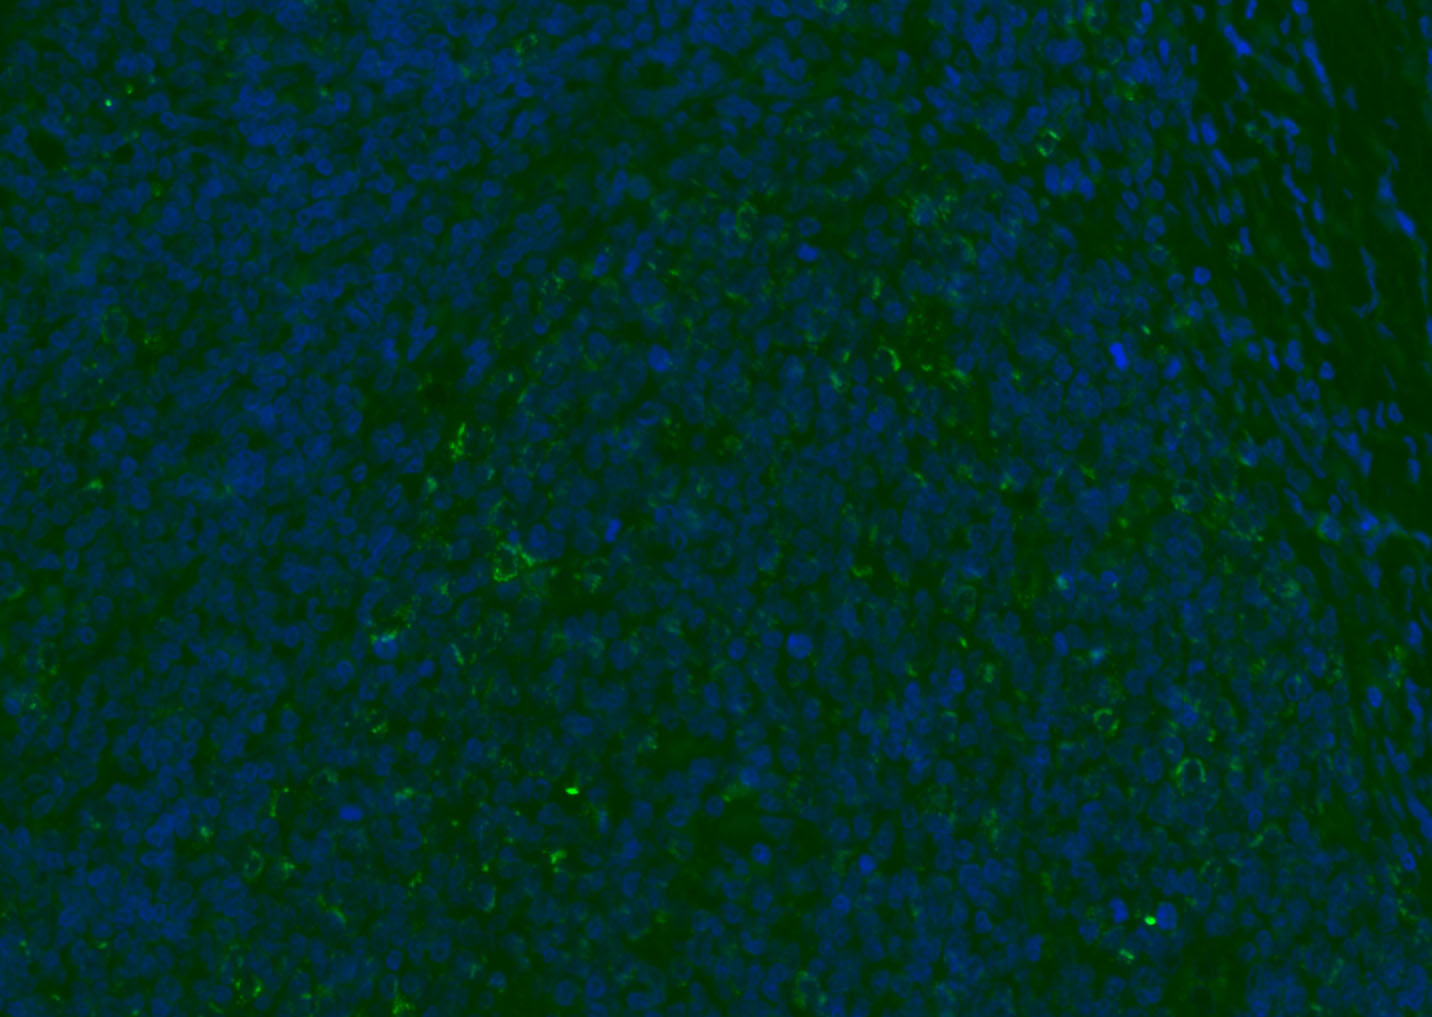

Paraformaldehyde-fixed, paraffin embedded (mouse thymus); Antigen retrieval by boiling in sodium citrate buffer (pH6.0) for 15min; Blocking buffer (normal goat serum) at 37°C for 30min; Antibody incubation with (CD8B) Polyclonal Antibody, Unconjugated (bs-4914R) at 1:200 overnight at 4°C, followed by a conjugated Goat Anti-Rabbit IgG antibody (bs-0295G-AF488) for 90 minutes, and DAPI for nuclei staining.